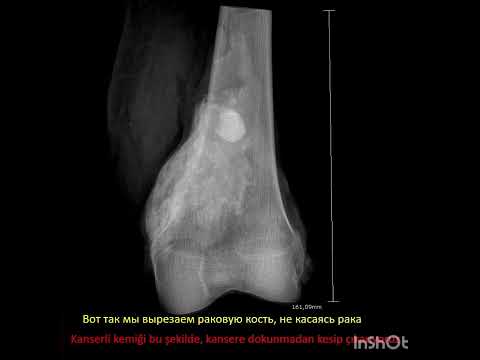

Kemik tümörlerinin tanısında basit röntgenler çok önem taşır ve doğru şekilde değerlendirildiğinde yeterli olabilir. Ancak kötü huylu olabileceği düşünülen ya da yumuşak doku tümörlerinde mutlaka MR çekilmelidir. MR kontrastlı olmalı ve yeterli kalitede olacak şekilde çekilmelidir. Aksi halde hasta tekrar MR çektirmek zorundadır. Kemik tümörlerinde zaman zaman bilgisayarlı tomografiden de yararlanılır. Ayrıca kemik taraması isteniyorsa, ya da tümörün diğer kemiklere yayılıp yayılmadığının anlaşılabilmesi için kemik sintigrafisi de önem taşır. PET ise son derece özel bir görüntüleme yöntemi olup henüz tanı almamış hastalar için yeri yoktur.

Doğru tedavi ancak doğru tanı konarak yapılabilir. Tedavide temel nokta, çok iyi planlanmış bir ameliyattır. Bu ameliyat bazen basitçe yapılabileceği gibi bazen de damar cerrahı, plastik cerrah, omurga cerrahı ve genel cerrahi gibi diğer branşların da operasyona dahil olmasını gerektirecek tarzda ağır ve kompleks operasyonlar şeklinde de olabilir. Ancak işin başında ortopedik onkolog olmalı ve tüm süreci doğru şekilde yönetmelidir. Aksi halde hasta uzvunu ya da hayatını kaybedebilir.